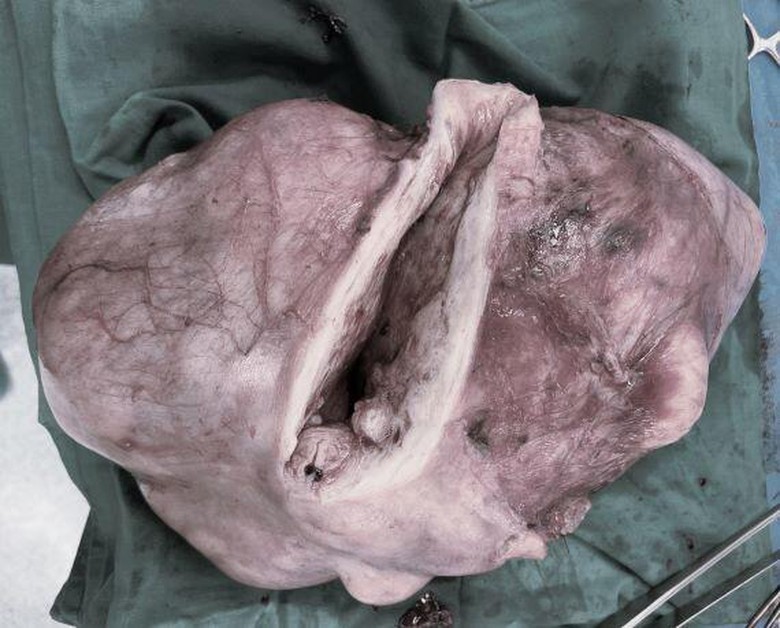

Các bác sĩ phẫu thuật, xử lý khối u xơ tử cung nặng hơn 3kg cho bệnh nhân người Tiền Giang

Sau hơn 2 giờ phẫu thuật, các bác sĩ đã đưa khối u nặng 3,2kg ra khỏi cơ thể chị Minh sau 10 năm “trú ẩn” dưới lớp thanh mạc tử cung, đồng thời, phải cắt bỏ tử cung để tránh tái phát.

Khối u xơ tử cung nặng 3,2kg của bệnh nhân được các bác sĩ phẫu thuật